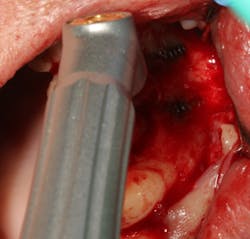

Failing implants that are afflicted with peri-implantitis usually are exposed to the same pathogens that affect natural teeth.7 These bacteria not only can coat an implant surface, but they also can be found in the surrounding peri-implant tissue. Complete removal of these bacteria via chemical detoxification of the residual implant socket and surrounding tissue can assist with removal of the pathogens (figure 3). Although both are effective, chemical modification with a neutral EDTA with a pH of 7.4 is a kinder alternative to tissue compared to 60% citric acid with a pH of 1. In addition, laser sterilization of the inflamed soft tissue surrounding the failed implant can help increase tissue tone during healing (figure 4).

Figure 4: Laser sterilization of soft-tissue flap during implant removal to facilitate healing